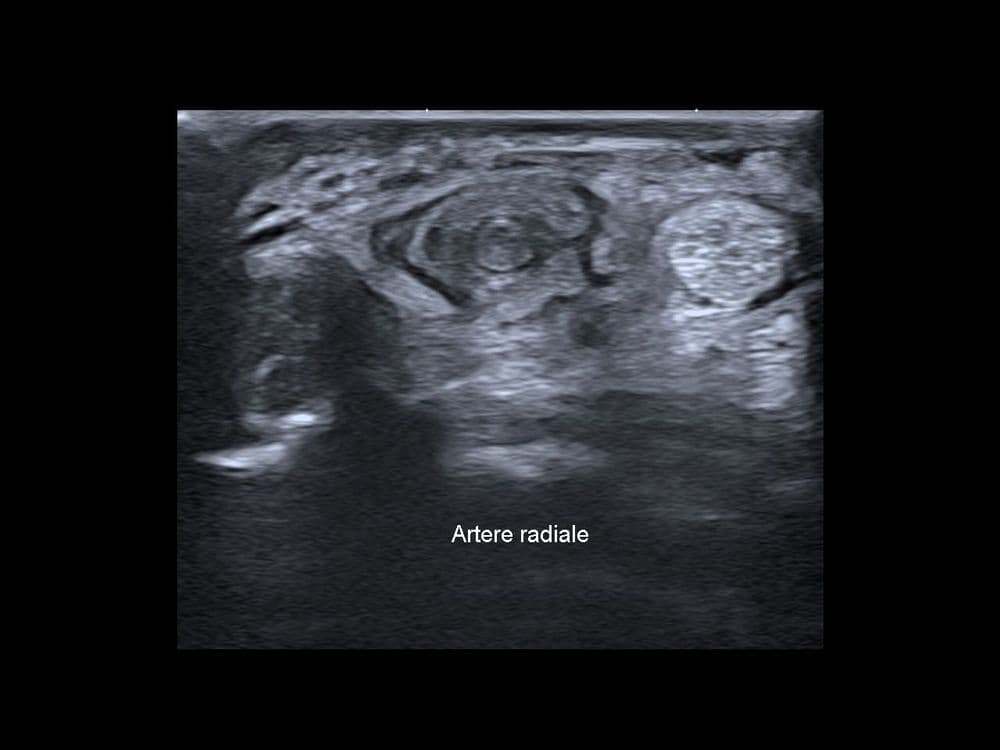

Pathologie vasculaire rare caractérisée par la formation d’un thrombus dans l’artère radiale sans antécédent de traumatisme.

US